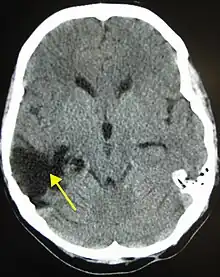

| A CT of the head years after a traumatic brain injury showing an empty space where the damage occurred, marked by the arrow | |

There are several imaging techniques that can aid in diagnosing and assessing the extent of brain damage, such as computed tomography (CT) scan, magnetic resonance imaging (MRI), diffusion tensor imaging (DTI) magnetic resonance spectroscopy (MRS), positron emission tomography (PET), and single-photon emission tomography (SPECT). CT scans and MRI are the two techniques widely used and are most effective. CT scans can show brain bleeds, fractures of the skull, fluid build up in the brain that will lead to increased cranial pressure.[36]